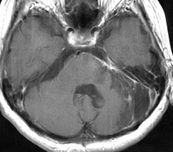

(術前MRI)

(術後MRI)

一方、この腫瘍は小さいのですが、三叉神経の圧迫により耐えがたい顔面痛により発見された髄膜腫です。当初手術を躊躇し鎮痛剤を服用しながら経過観察しておりましたが、症状が改善されなかったため、手術を行いました。腫瘍は全摘され、術前に鎮痛剤で改善しなかった顔面痛は、術後には完全に消失しました。勿論、鎮痛剤を服用する必要も全くなくなりました。思い切って手術を決断してよかったと大変満足いただけました。 このように手術をしないと症状が改善されない髄膜腫もあります。